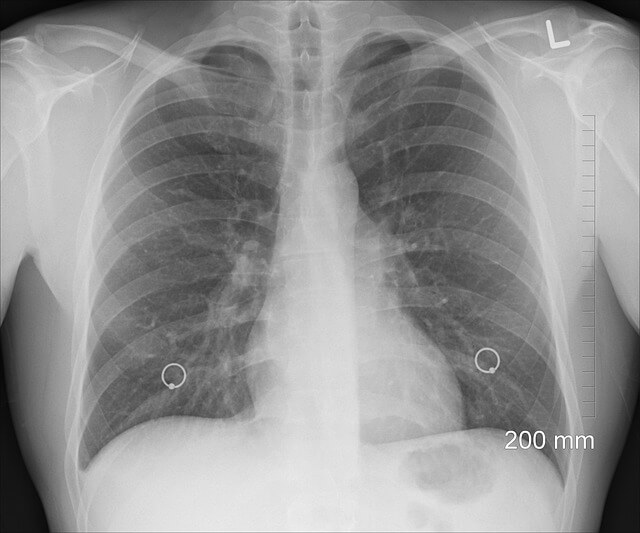

기흉의 특징적인 증상 중 하나는 갑작스럽고 날카로운 가슴 통증입니다. 통증은 종종 한쪽으로 나타나고 흡입하는 동안 더 심할 수 있습니다. 호흡 곤란은 또 다른 흔한 증상입니다. 이것은 기흉의 크기에 따라 경미한 것부터 심각한 것까지 다양할 수 있습니다. 또한 폐 기능 저하로 인해 평소보다 더 빠르게 호흡할 수 있습니다. 어떤 사람들은 더 깊은 흡입과 관련된 고통을 최소화하기 위해 본능적으로 얕은 호흡을 할 수 있습니다. 심한 경우 산소 부족으로 인해 입술과 손가락 끝이 푸른빛을 띠게 될 수 있으며, 이를 청색증이라고 합니다. 신체검사 중에 흉부의 환부에서 호흡음이 감소하거나 없는 것을 관찰할 수 있습니다. 더 심한 경우에는 피부 아래 조직으로 공기가 빠져나가서 피부 아래 폐기종으로 알려진 삐걱거리는 소리나 감각을 유발할 수 있습니다. 이는 종종 가슴과 목 주변의 피부를 눌러 느낄 수 있습니다. 일부 사람들은 마른기침을 할 수 있습니다. 기흉의 크기에 따라 증상이 달라질 수 있다는 점에 유의하는 것이 중요합니다. 작은 기흉은 가벼운 증상을 유발하거나 심지어 무증상일 수도 있지만, 큰 기흉은 더 심각한 호흡곤란을 유발할 수 있어 즉각적인 진료가 필요합니다. 기흉이 의심되거나 갑작스러운 가슴통증과 호흡곤란이 나타나면 신속히 진료를 받는 것이 중요합니다.

기흉의 치료와 회복은 상태의 중증도와 1차 자발성 기흉(폐질환 없이 발생)인지 2차 자발성 기흉(폐질환이 있는 상태에서 발생)인지에 따라 달라집니다. 작고 무증상인 기흉은 적극적인 치료가 필요하지 않을 수도 있습니다. 경우에 따라 의사는 기흉이 스스로 해결되는지 확인하기 위해 환자를 관찰하고 모니터링하는 것을 선택할 수도 있습니다. 환자에게 보조 산소를 제공하면 흉막 공간에서 공기가 재흡수되고 폐의 재팽창을 촉진하는 데 도움이 될 수 있습니다. 큰 기흉의 경우 또는 증상이 있는 경우 의료 제공자가 바늘 흡인을 수행하거나 흉막 공간의 공기를 제거하기 위해 흉관을 삽입할 수 있습니다. 이는 폐를 다시 확장하는 데 도움이 됩니다. 흉막 공간에 흉관을 삽입(튜브 흉곽 절제술)하여 공기 또는 액체를 제거하고 폐가 다시 팽창하도록 할 수 있습니다. 이것은 증상이 더 심각한 경우에 수행됩니다. 재발성 또는 지속성 기흉의 경우 흉막염이라고 불리는 시술을 고려할 수 있습니다. 여기에는 흉막 공간에 물질(탈크 등)을 도입하여 염증을 일으키고 폐와 흉벽 사이에 유착을 일으켜 재발을 방지하는 것이 포함됩니다. 어떤 경우에는, 특히 재발하는 기흉 또는 특정한 기저 폐 상태의 경우, 외과적 개입이 권장될 수 있습니다. 이것은 수포(공기로 가득 찬 비정상적인 공간)를 없애고, 미래의 기흉을 예방하기 위한 흉강경 또는 개흉술과 같은 절차를 포함할 수 있습니다. 회복 시간은 기흉의 중증도와 선택한 치료법에 따라 다릅니다. 폐가 다시 팽창한 후에는 재발이 없는지 확인하기 위해 환자를 일정 기간 동안 모니터링해야 할 수도 있습니다. 회복을 평가하기 위해 흉부 X선과 같은 후속 영상 촬영을 수행할 수도 있습니다. 기흉이 있는 사람은 의사의 권장 사항을 따르고 증상이 악화되면 후속 진료를 받는 것이 필수적입니다. 치료에 대한 구체적인 접근 방식은 의료진이 개별 환자 요인과 기흉의 특성을 기반으로 결정할 것입니다.